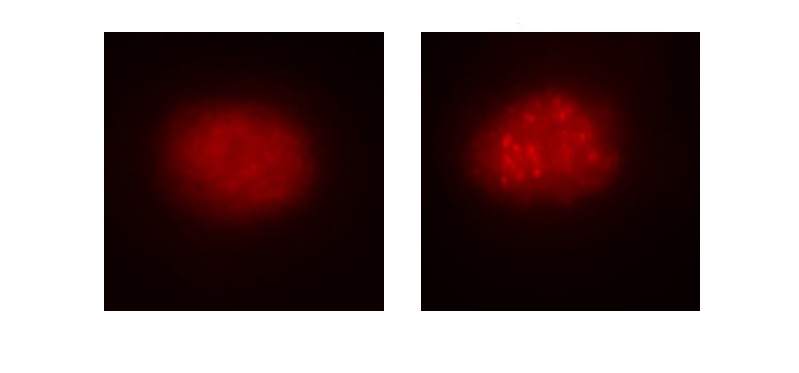

Desarrollan dos modelos de carcinoma neuroendocrino de célula grande y microcítico de pulmón

15/10/2019